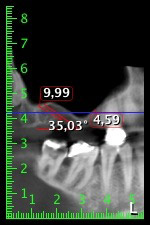

Die 59-jährige Patientin wurde mit einer fortgeschrittenen Parodontitis vorstellig, beschrieb ein ungutes Gefühl und einen schlechten Geschmack ausgehend vom ersten Quadranten distal. Die klinische Untersuchung zeigte allgemein erhöhte Taschentiefen und einen stark fortgeschrittenen Knochenabbau in regio 16 und 14. Die radiologische Untersuchung untermauerte den Befund (Abb. 1). Die Zähne 16 und 14 waren nicht zu erhalten.